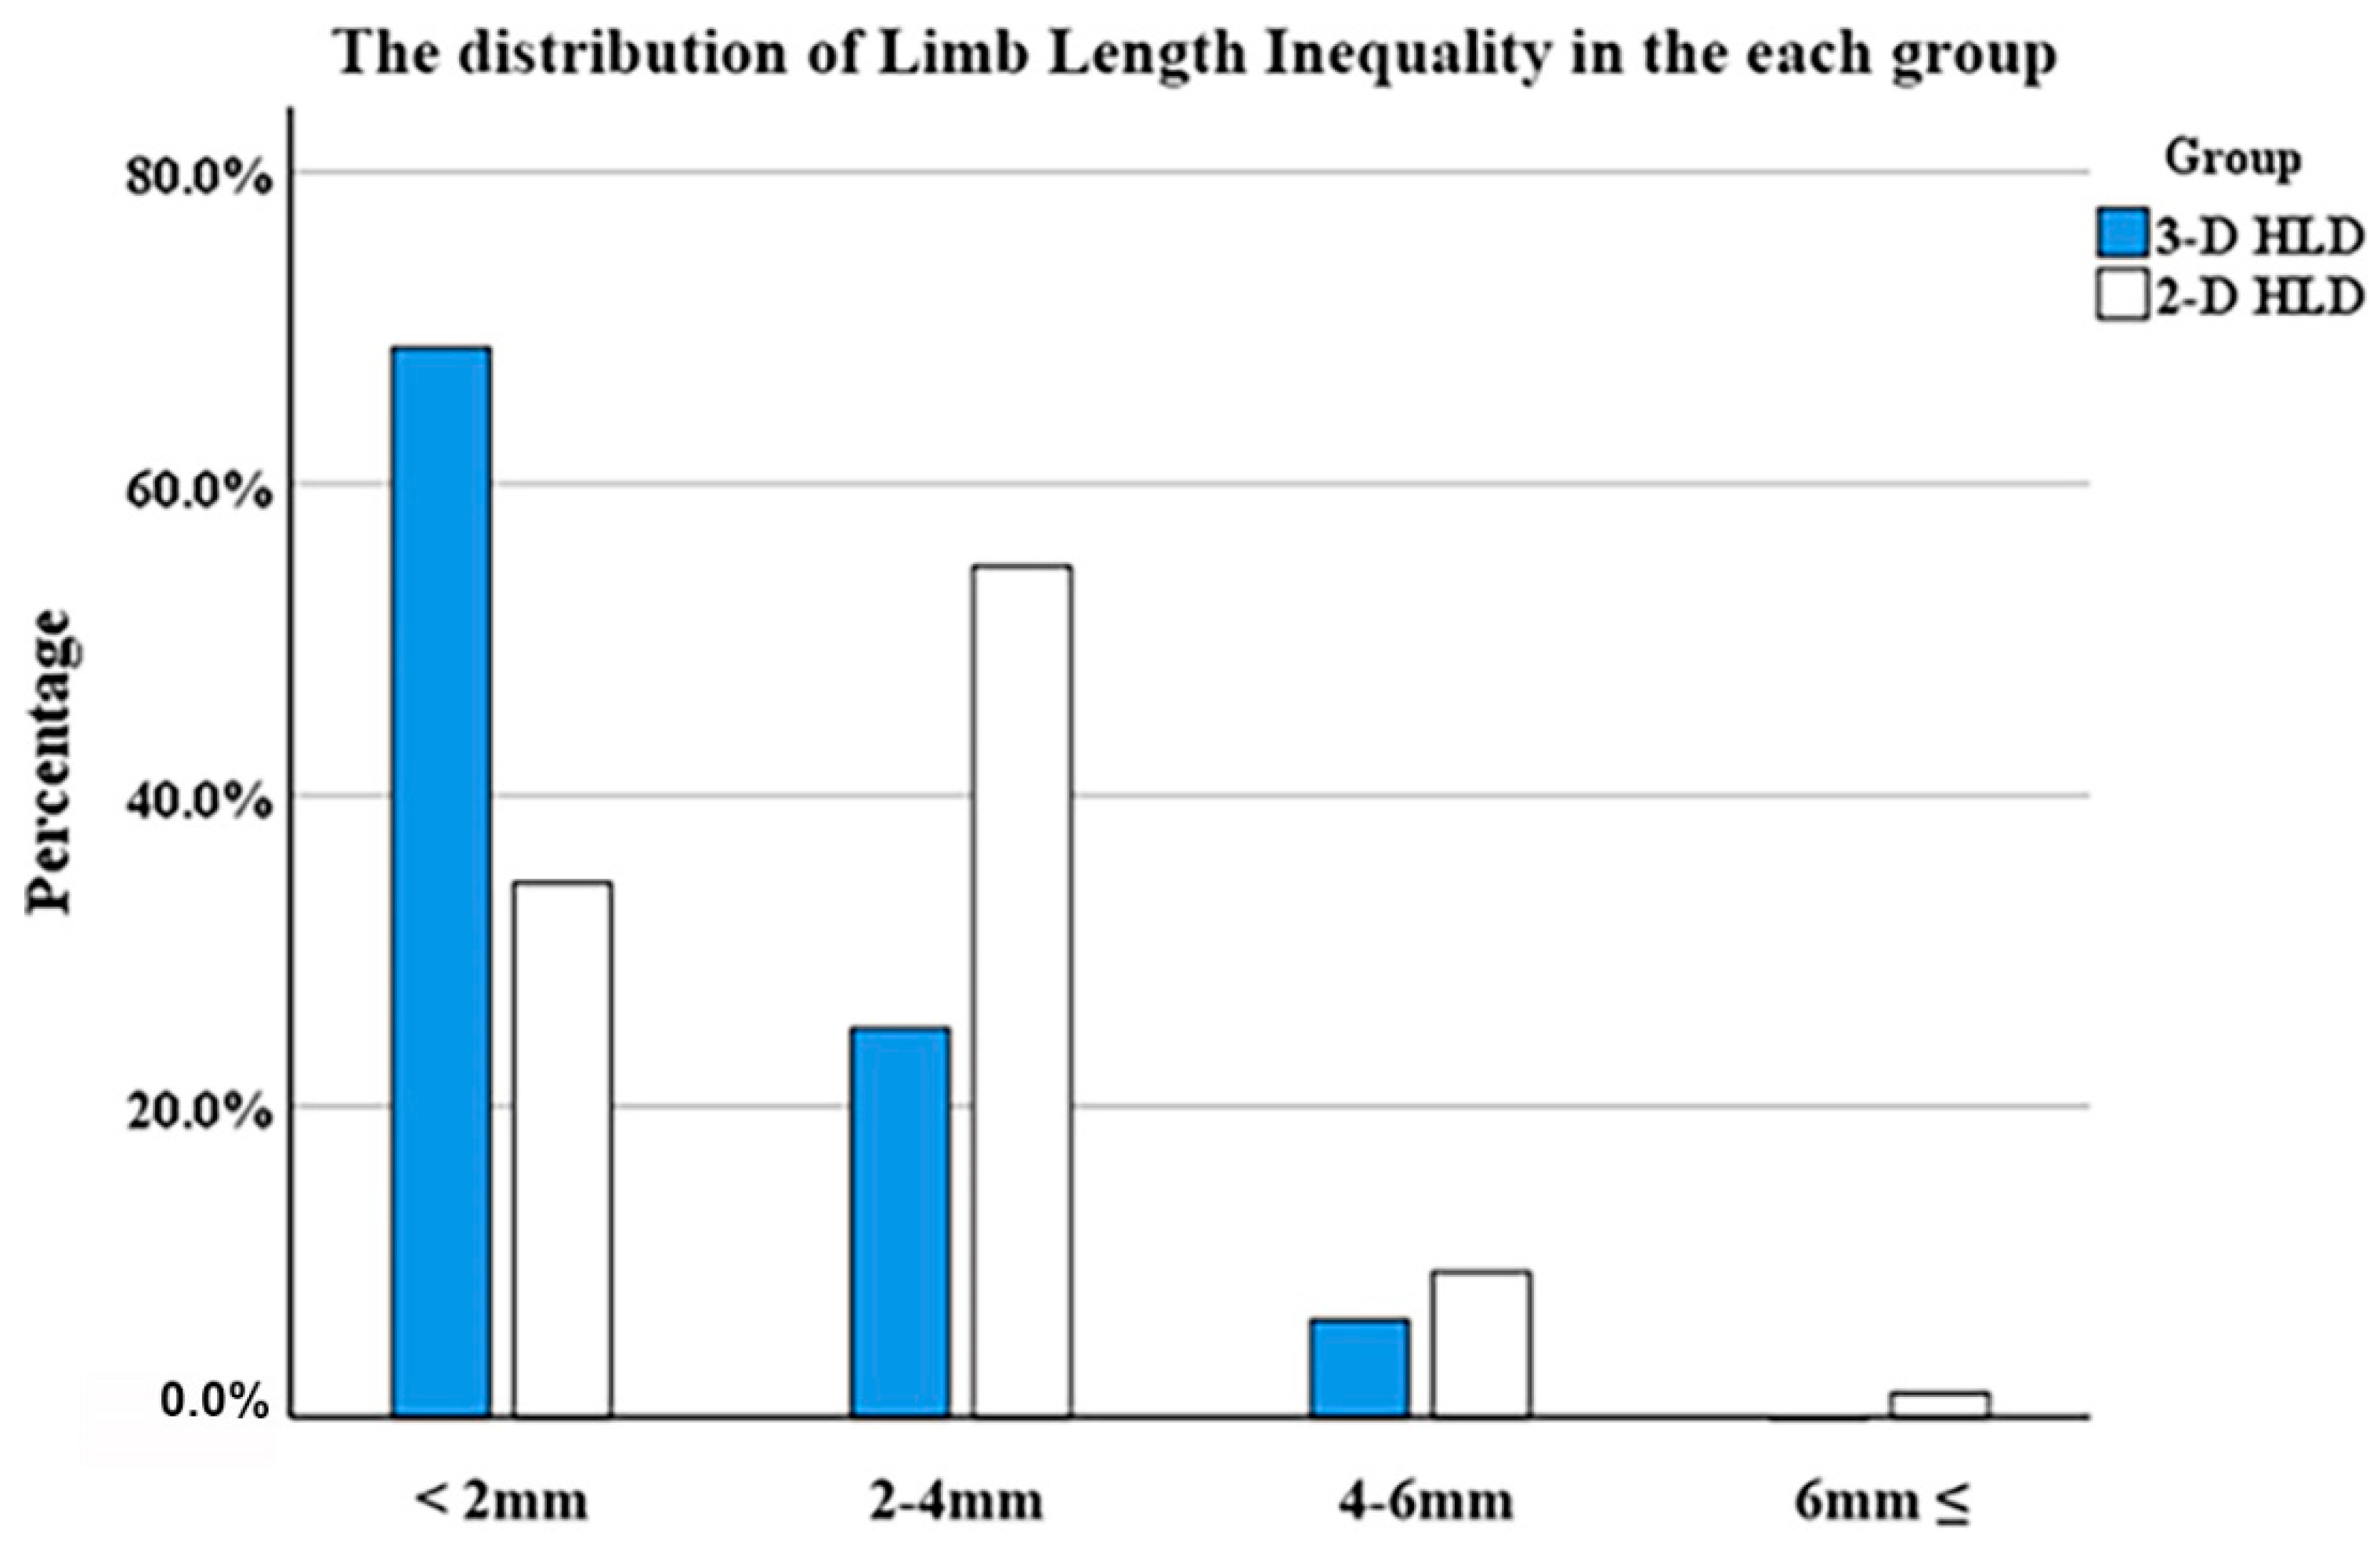

| Mean LLD | 1.6 ± 1.2 | 1.1 ± 1.2 | 0.024 |

| <2 mm | 22 (34.4%) | 44 (68.8%) | |

| 2–4 mm | 37 (57.8%) | 16 (25.0%) | |

| 4–6 mm | 4 (6.3%) | 4 (6.3%) | |

| ≥6 mm | 1 (1.6%) | 0 (0.0%) | 0.001 |